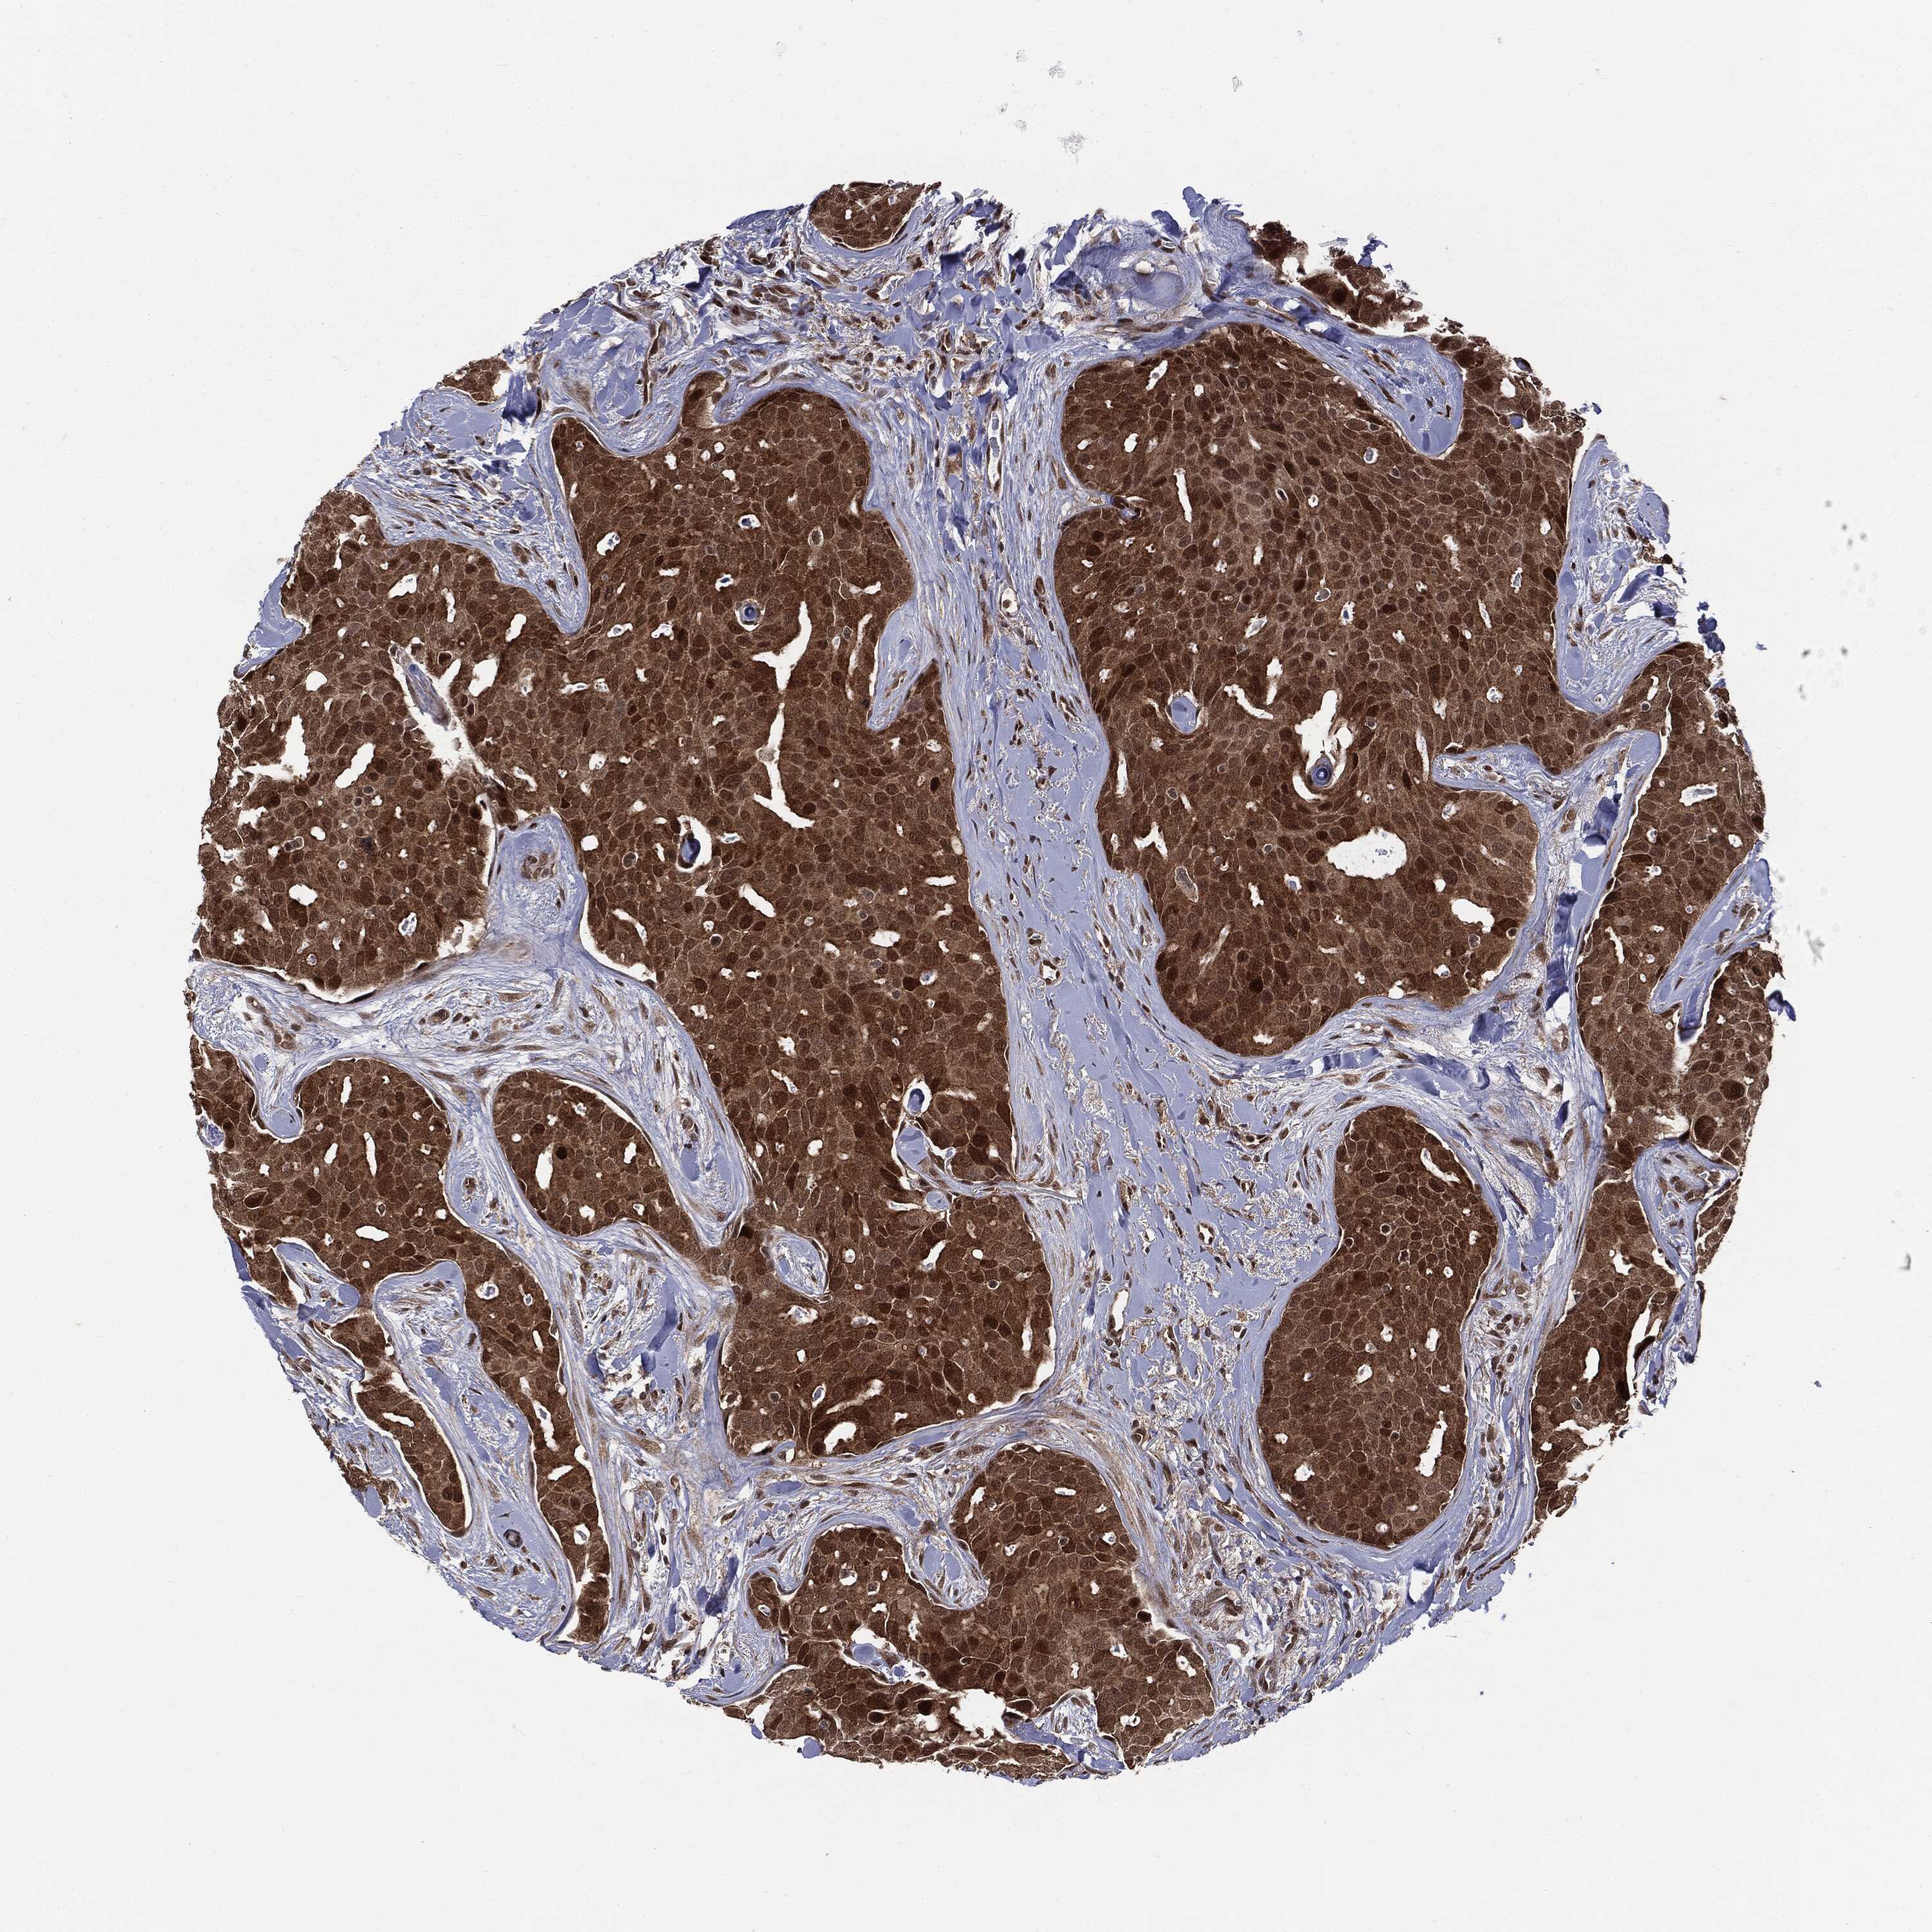

CANCER BREAST CANCER Show tissue menu

BRCA TCGA BRCA VALIDATION PROTEIN EXPRESSION

ANTIBODIES

AND

VALIDATION